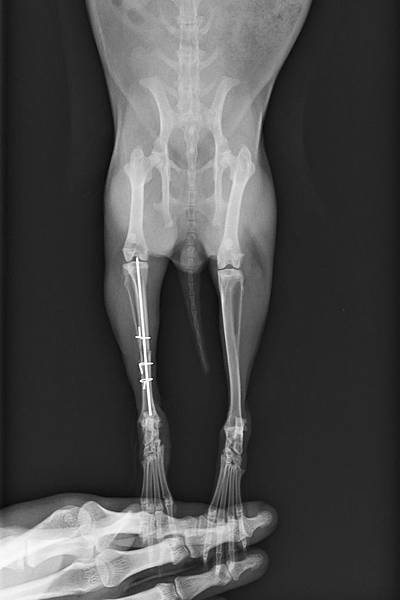

70_205_20120329235008.0 手術後側照

70_206_20120329235205.0  手術後正照

手術採取骨髓內釘合併環紮鋼線修復,手術後配合軟包紮及限制活動4周,癒合良好